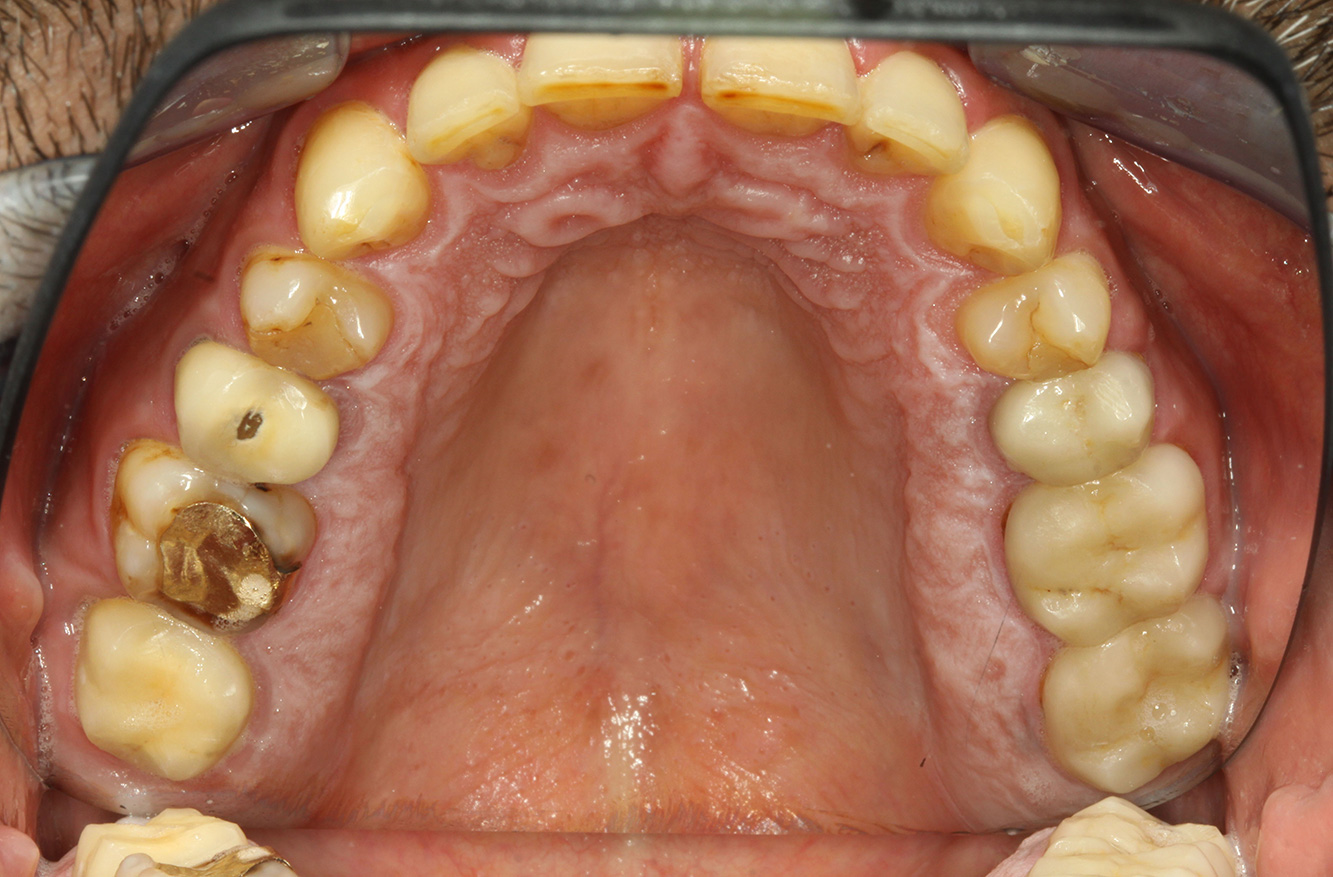

Il paziente ha 39 anni e in passato è stato sottoposto ad un intervento per la sostituzione della valvola aortica dovuta a insufficienza valvolare ed endocardite. Assume regolarmente l'ASS 100 come anticoagulante. Per quel che riguarda lo stile di vita, il regime alimentare seguito dal paziente è classificato come “dieta che favorisce la formazione della carie”, per via del consumo regolare di cibi ad alto contenuto di zuccheri e dei sei-sette pasti consumati al giorno. La salute orale del paziente indica un rischio moderato di carie, con lesioni attive. Il rischio di parodontite è basso, tuttavia il paziente è affetto da gengivite. Si formulano quindi i seguenti consigli per il trattamento di profilassi.

Per la seduta di profilassi non si possono formulare consigli per strumenti specifici. Si può ricorrere a un'applicazione mirata di air-polishing e lucidatura con testina rotante per rimuovere delicatamente placca e discromie lungo i margini del restauro e per ridurre le nicchie dove i batteri cariogeni possono formare nuove colonie (19).

A causa delle lesioni cariose attive e del rischio ad esse associato di progressione, si consiglia un intervallo di richiamo ravvicinato di tre-quattro mesi.